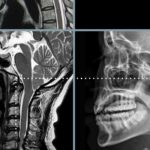

Cervical Pathology